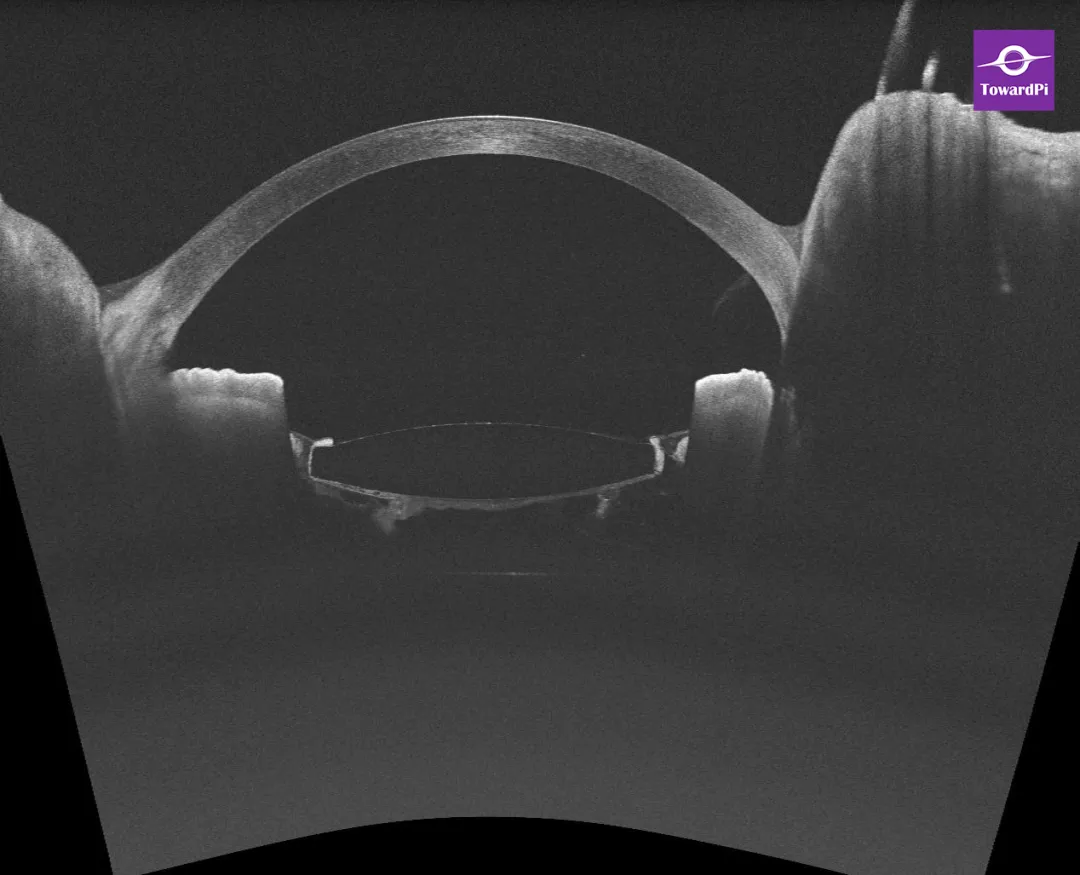

图6. 前节OCT:后囊膜不连续中央缺失,囊袋内混浊积液消失,IOL后可见部分絮状玻璃体。

图7. 前节3D扫描:后囊膜中央切开,后凸明显消失。